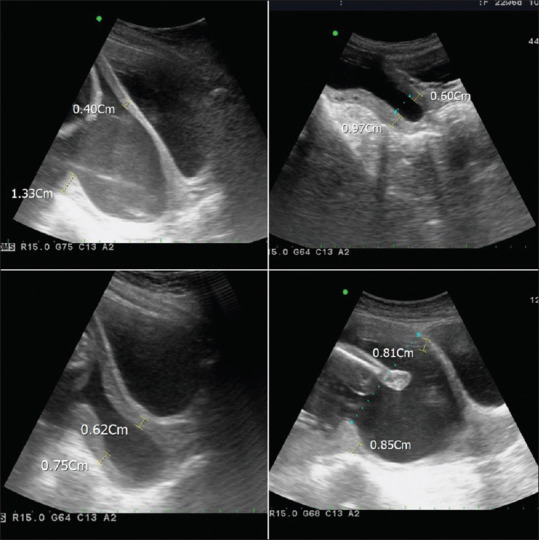

Cervical insufficiency poses risks for premature birth and neonatal outcomes. Preoperative sonography aids in the diagnosis and therapeutic considerations. Cervical cerclage is effective but carries risks. In our case series, 8 cases failed to complete emergent cerclage, leading to adverse outcomes. Analysis of preoperative images revealed thicker cervixes and cervical strictures may affect the surgical outcomes. Larger studies are needed to determine the reliable cutoff values. Preoperative assessment is crucial to inform treatment decisions.

宫颈功能不全对早产和新生儿结局构成风险。术前超声检查有助于诊断和治疗。宫颈环切术是有效的,但也有风险。在我们的病例系列中,有8例未能完成紧急循环,导致不良后果。术前图像分析显示宫颈较厚和宫颈狭窄可能影响手术结果。需要更大规模的研究来确定可靠的临界值。术前评估对决定治疗至关重要。